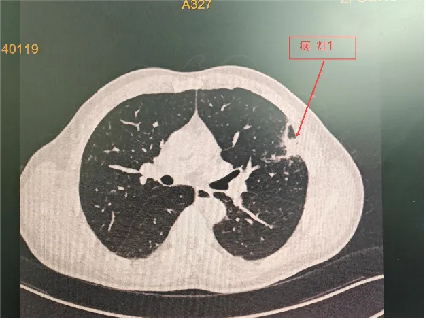

程大叔的胸部CT

程大叔的女儿立即将他带到自贡市第四人民医院呼吸与危重症医学科,接诊的医生阅读胸部CT检查单后并分析,考虑良性的炎性病灶可能性更大,以最快的速度安排了肺穿刺活检